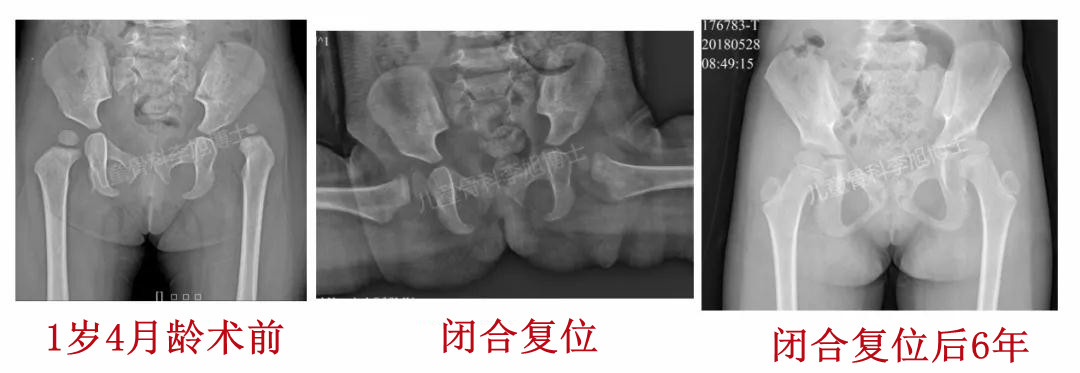

1、12月龄以内的孩子,闭合复位往往能够成功!

3、18月龄以内的孩子,应该首先尝试闭合复位,推荐在复位之前先进行悬吊牵引!如果初次闭合失败,那么再次去争取闭合的成功可能性极低,应该当机立断选择切开!切开不受年龄的限制,低龄不是切开的禁忌!!